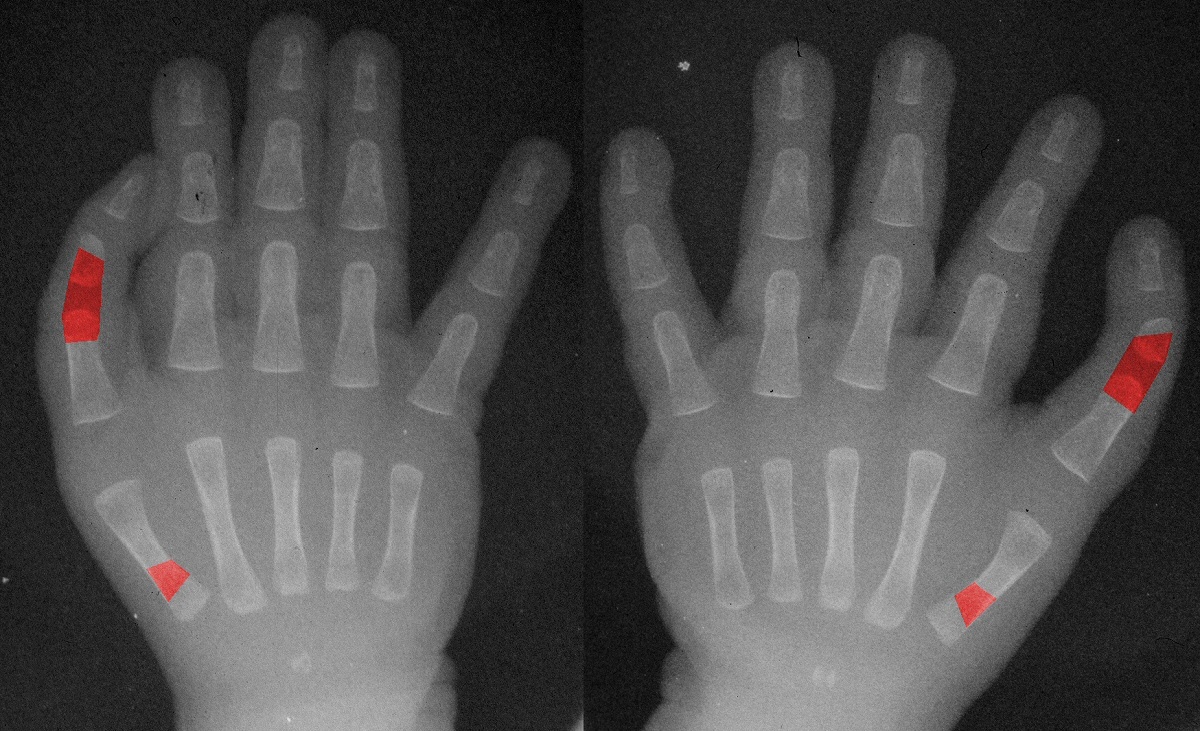

| Immediately postop. |

| Right hand. |

| Immediately preop. |

| The same type of procedure was performed on both hands at the same setting. This included a shortening/straightening proximal interphalangeal joint fusion and a shortening/pronating/abducting metacarpal osteotomy, along with extensor tendon shortening. Bone fixation at each site was with an intramedullary absorbable pin and intraosseous PDS sutures. Red areas are the areas of skeletal removal. |